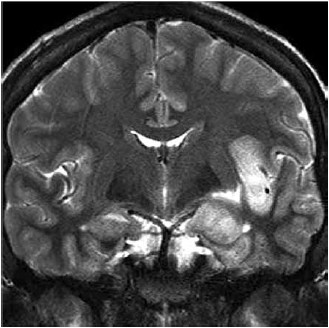

Homem de 63 anos com histórico de hipertensão, tabagismo (30 maços-ano) e etilismo é internado com febre e convulsões de início recente. Ele apresenta espasmos faciais, tremores nos braços e pernas e alguns episódios de tremores aparentemente generalizados que duram 1 hora. Ele recebe o total de 20 mg de diazepam intravenoso, o que interrompe a atividade convulsiva. Ao chegar na UTI, o estado mental começa a piorar e ele é intubado e colocado em ventilação mecânica. A ressonância magnética (coronal, T2) realizada é mostrada a seguir.

(Arquivo pessoal: imagem usada com autorização.)

Considerando a principal hipótese diagnóstica, é correto afirmar: